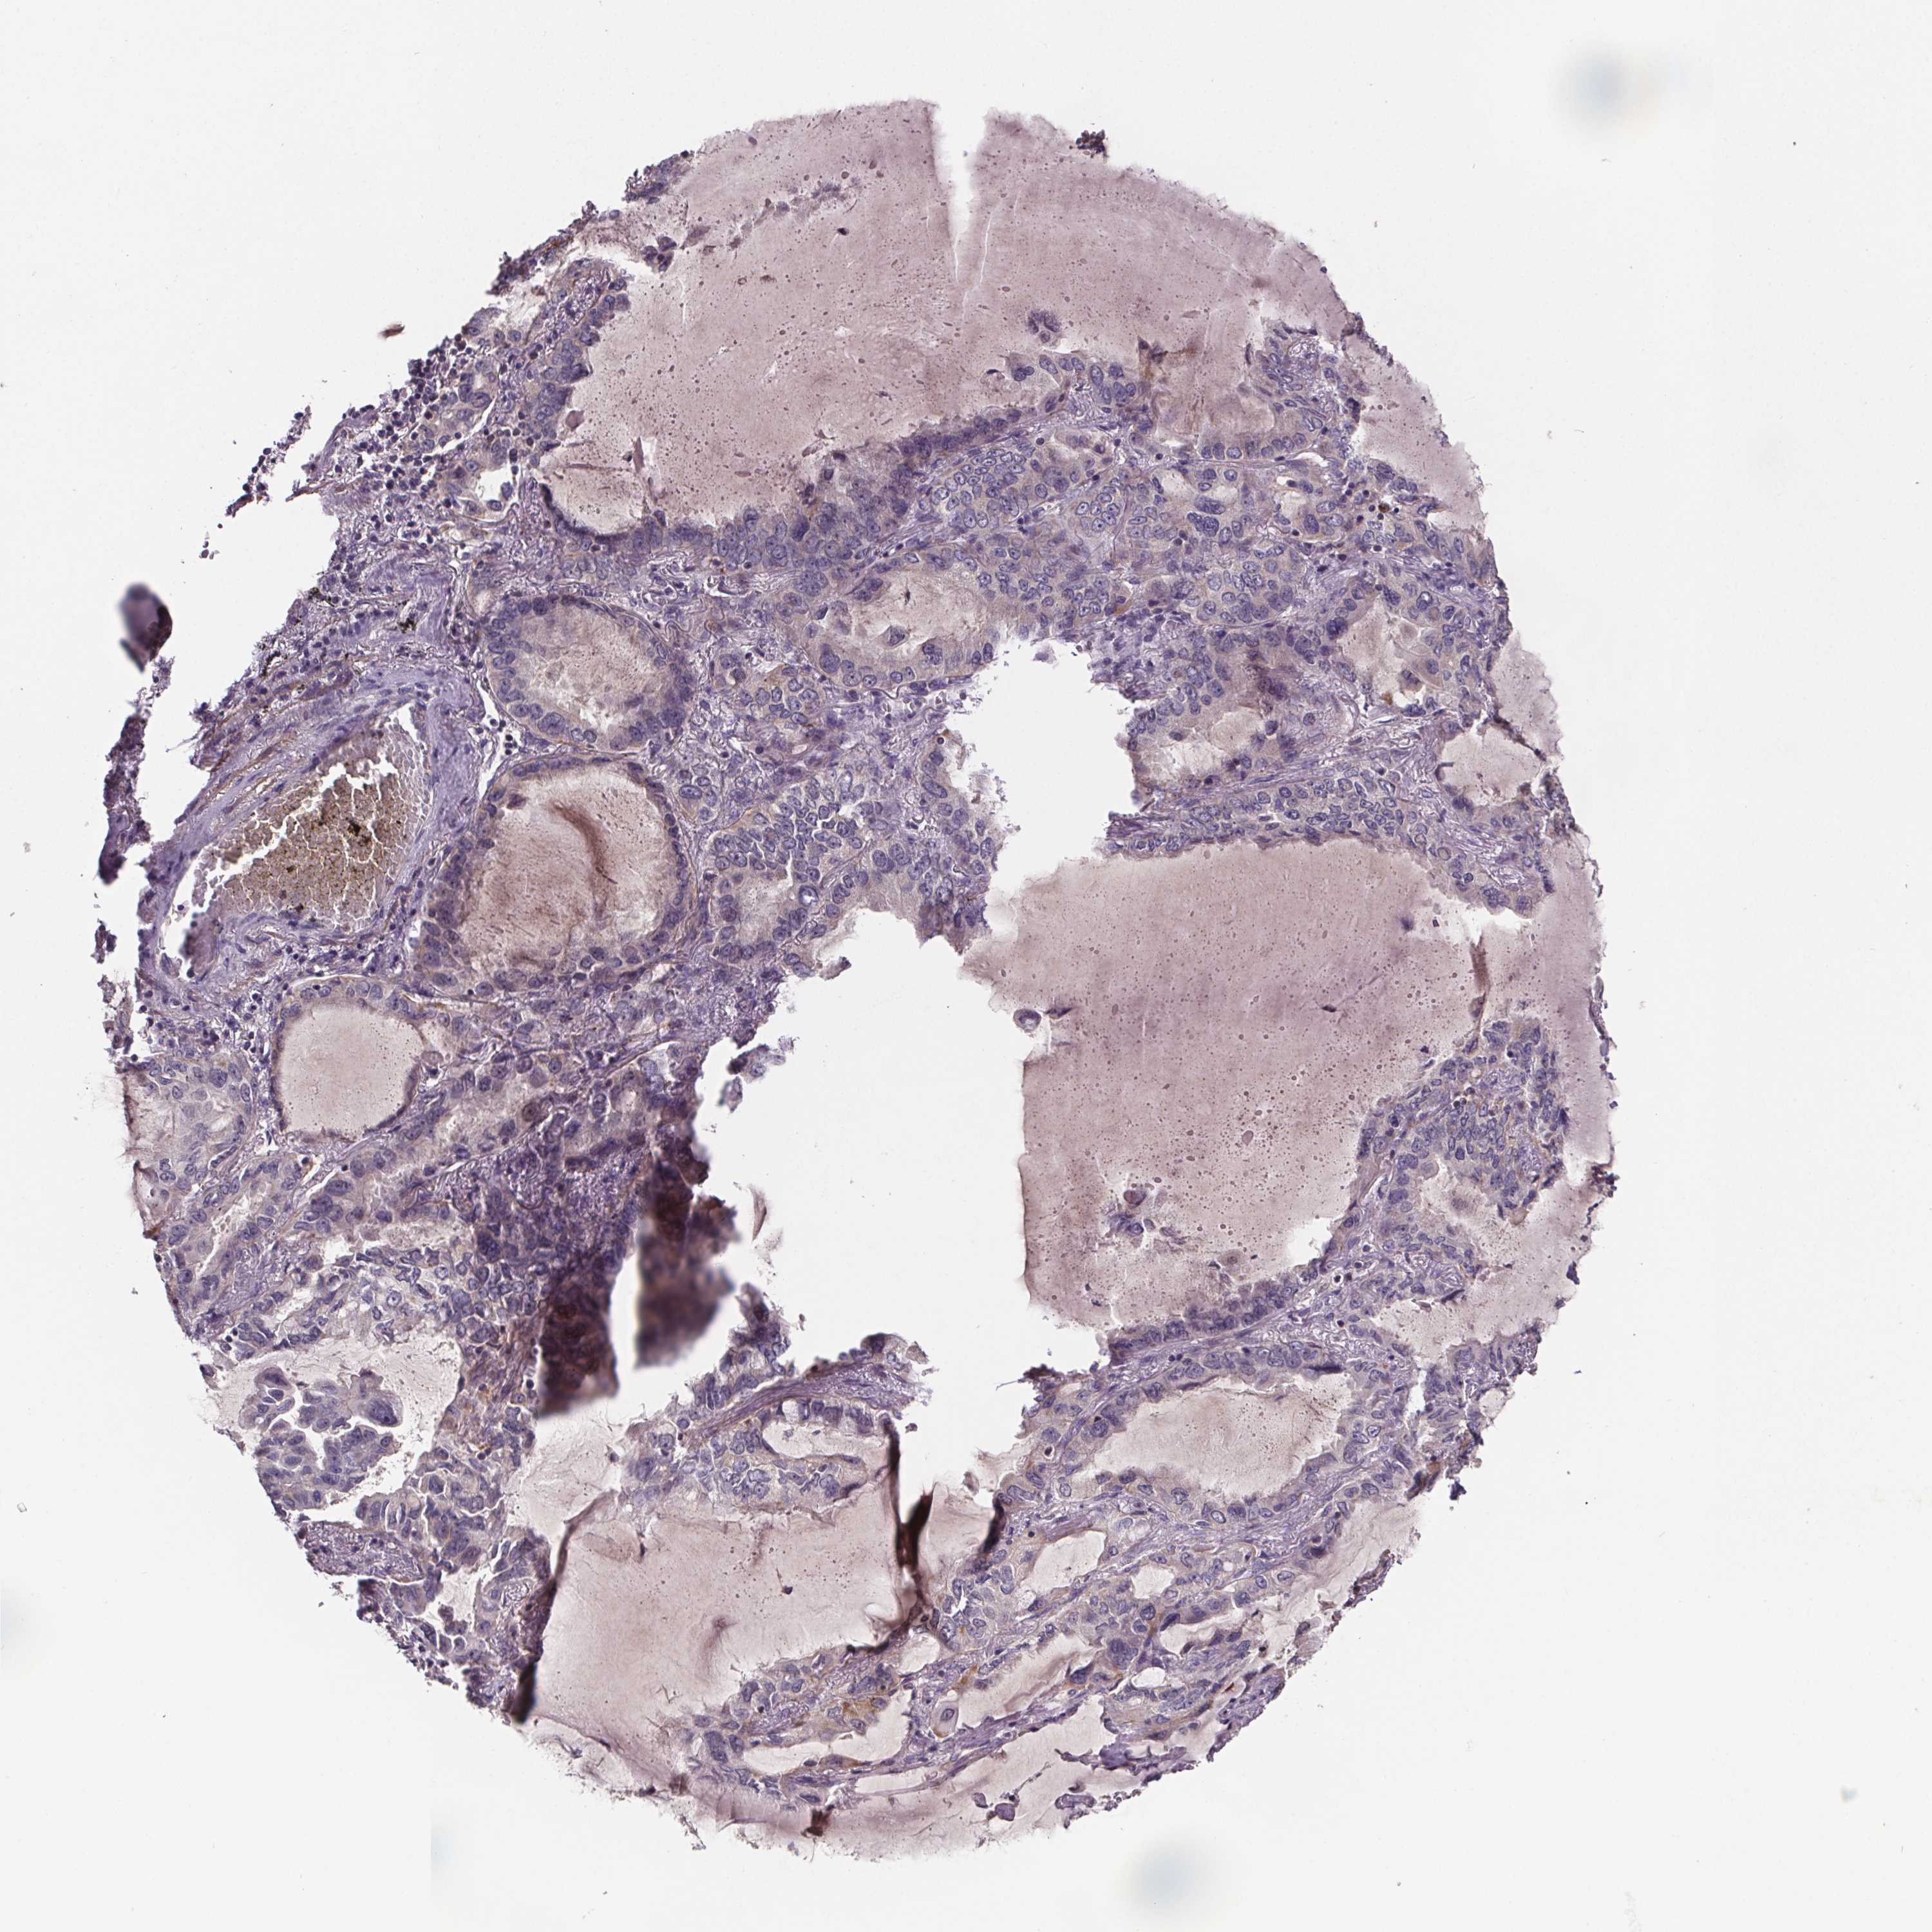

CANCER LUNG CANCER Show tissue menu

LUAD TCGA LUAD VALIDATION LUSC TCGA LUSC VALIDATION PROTEIN LUAD CPTAC PROTEIN LUSC CPTAC PROTEIN EXPRESSION